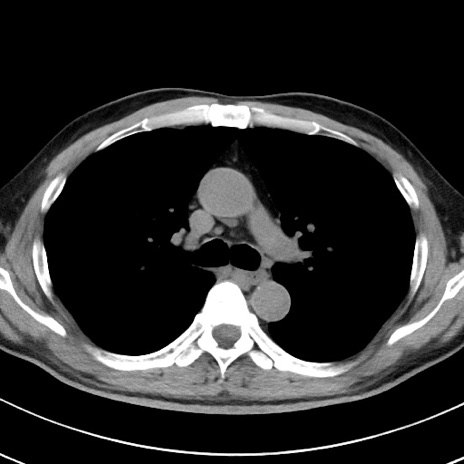

【腹部TIPS】症例29 参考症例 CT(横断像)

症例

70歳代男性